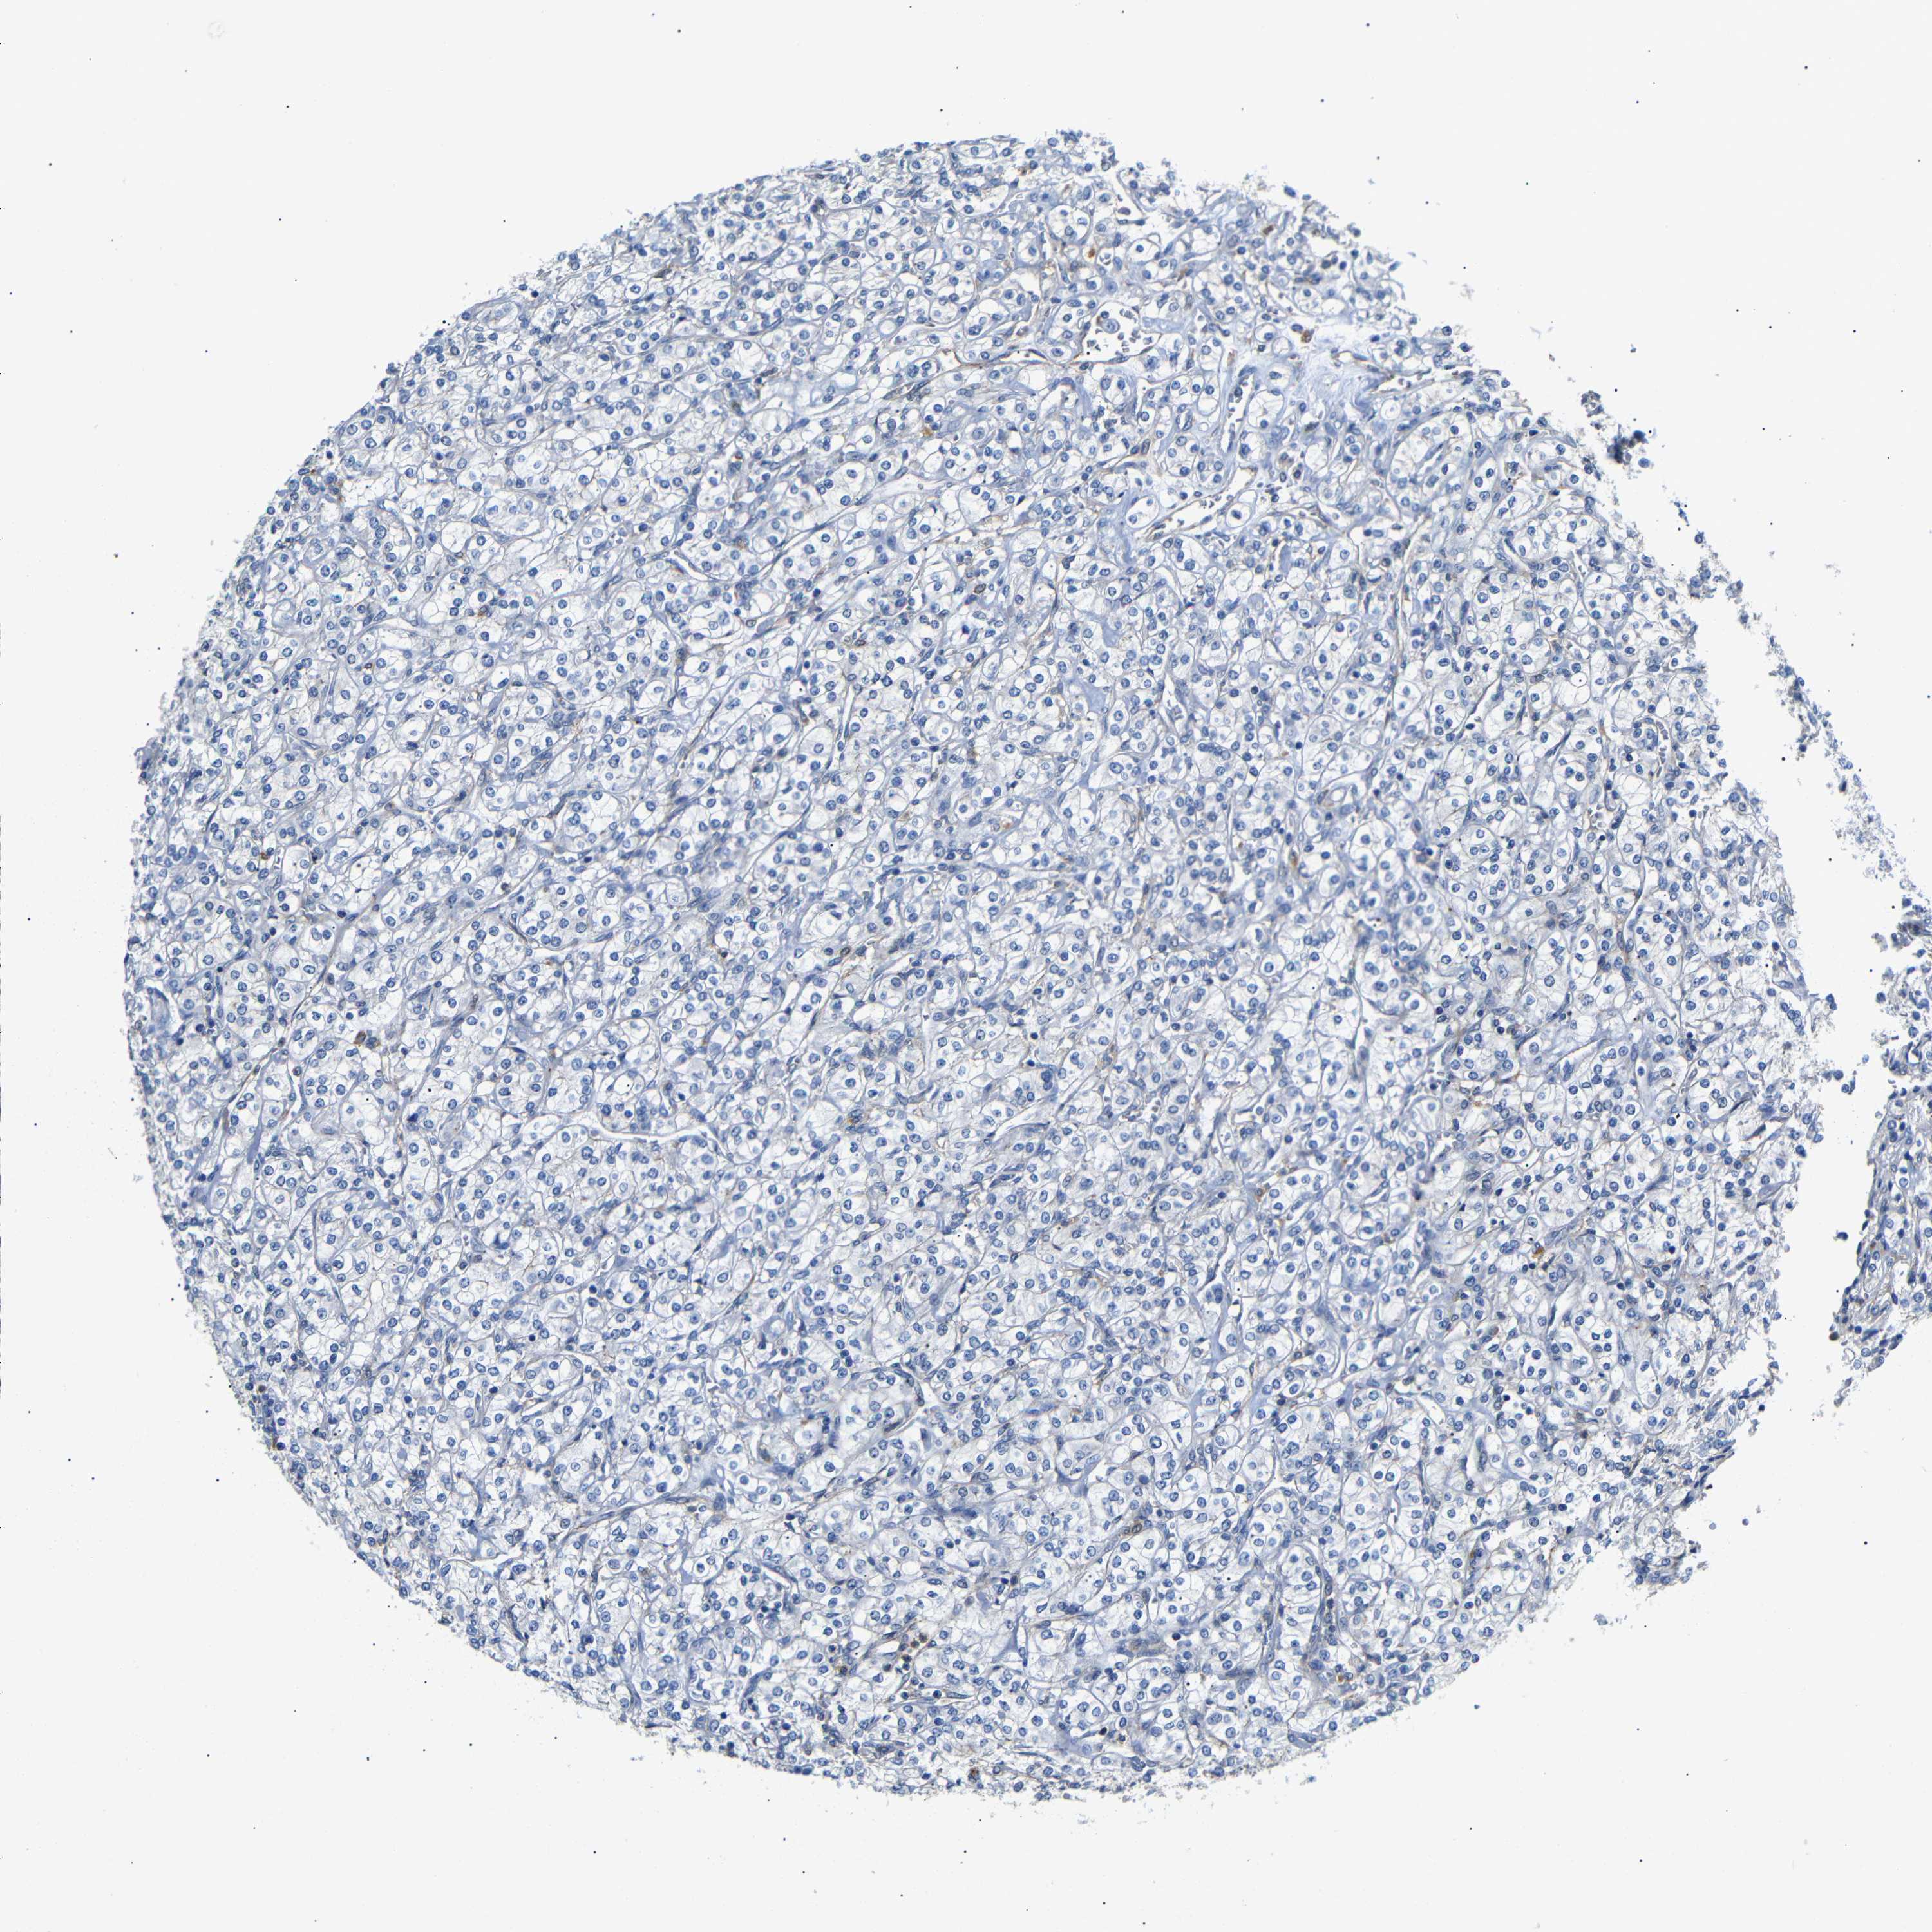

KIDNEY RENAL CLEAR CELL CARCINOMA (VALIDATION) - Interactive survival scatter ploti

SDCBP is not prognostic in Kidney Renal Clear Cell Carcinoma (validation)

: 146.98

Average pTPM 183.9

Number of samples 100